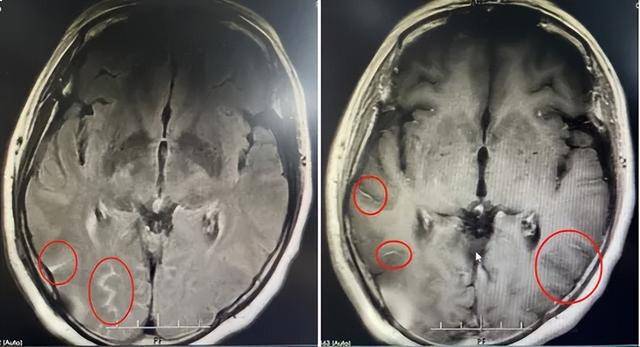

妇人颅内压增高,感染隐球菌脑膜炎。(图 :《鲁中晨报》)

医师诊断后发现,妇人颅内压增高,不但挤压了旁边的脑组织,还造成脑中较长颅神经的损伤,导致视力下降、听力损伤等不可逆的伤害。不过经过手术以及一系列的治疗,妇人的头痛症状好转,左眼视力也恢复正常。而造成妇人罹病的罪魁祸首,竟是菜市场的“家禽”,由于妇人平常负责买菜做饭,所以经常会接触家禽。